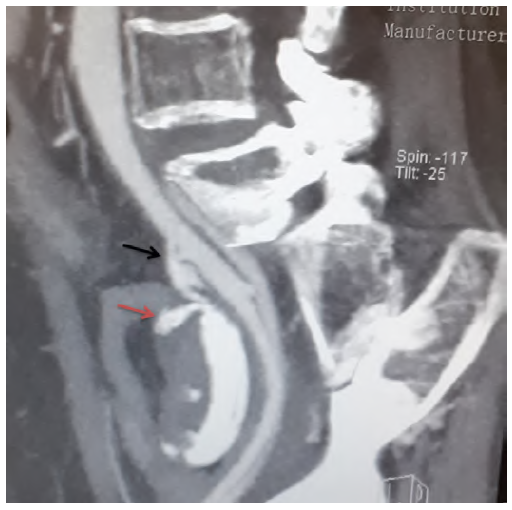

A 84-year-old female, with history of lupus, underwent pelvic exenteration, lymphadenectomy and cutaneous ureteroileostomy for high-grade urothelial carcinoma. In the postoperative period, an ileostomy with reconstruction of ureteroileal anastomoses and bilateral nephrostomies was required due to intestinal dehiscence with an abscess. She completed broad-spectrum antibiotics and antifungal therapy and was discharged with catheterized ureters. About 4 months later, the patient presented to the emergency department (ED) with gross hematuria. The blood work revealed 11g/dl of haemoglobin. Having been discharged, she returned to the ED the next day, hypotensive (94/61mmHg) with significant hematuria from ureteroileostomy, while haemoglobin had dropped to 8 g/dl, requiring aminergic support and the transfusion of two units of blood. Computed tomography (CT) angiography did not identify active bleeding and suggested integrity of the excretory system. She remained hospitalized under surveillance until she had another episode of hemorrhagic shock (blood pressure 49/23mmHg) with profuse bleeding through the ureteroileostomy, with a drop of hemoglobin to 5.5 g/dl. A new CT angiography was performed identified a fistula between the right common iliac artery and the ureteroileostomy (Figures 1 and 2). She underwent emergency angiography and fistula exclusion with a covered stent with intentional hypogastric coverage (the contralateral hypogastric was patent) given the short sealing length and the imminent risk of death (Figure 3). During the remaining hospital stay, there were no bleeding recurrences, and the patient was discharged on the 21st postoperative day after completing antibiotic therapy (meropenem and linezolid) and antifungal medication (micafungin) directed to urine cultures (isolated: multidrug resistant Staphylococcus aureus, Enterococcus faecium, Candida albicans). About one month later she was hospitalized again for acute kidney injury with ionic changes and complicated urinary tract infection, ending up dying from this complication.

Figure 2 Preoperative computed tomography angiography (sagittal). AUF on sagittal computed tomography angiography (black arrow). Red arrow points to the ureteroileostomy with contrast inside.